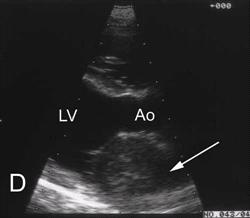

Figure 4.

Right parasternal long-axis 2-dimensional echocardiogram obtained in diastole showing the classic findings of cardiac tamponade. Notice the anechoic space surrounding the heart and the marked collapse of the right atrium (Arrow). Click on image to see a larger view.

Echocardiography is the most sensitive and specific non-invasive method of detecting pericardial effusion currently available. The hemodynamic consequences of pericardial effusion depend not only on the amount of pericardial effusion present, but also on the rapidity with which the effusion has accumulated. A small or moderate amount of fluid accumulating rapidly (left atrial rupture) may produce significant hemodynamic compromise, while a large amount of effusion accumulating over months may have little hemodynamic effect. These principles should be remembered when assessing the significance of an echocardiographically-detected pericardial effusion. Echocardiography can detect as little as 15 ml of intrapericardial fluid. An anechoic space between the epicardium and pericardium is the classic echocardiographic finding in pericardial effusion. Cardiac motion is commonly abnormal often with dramatic side-to-side movement and diastolic compression (Figure 4). Overall cardiac chamber size is usually diminished due to impaired cardiac filling. Intrapericardiac or cardiac mass lesions may be visualized (Figures 5A-D).